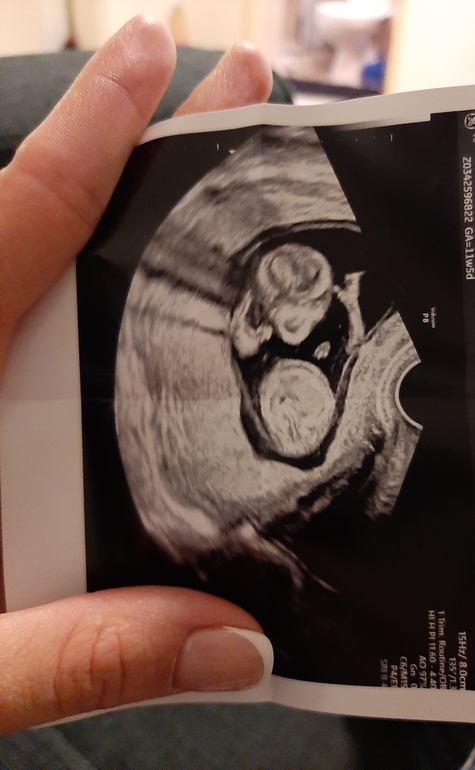

Срок сегодня 16,6 но он крупный и опережает минимум на неделю)